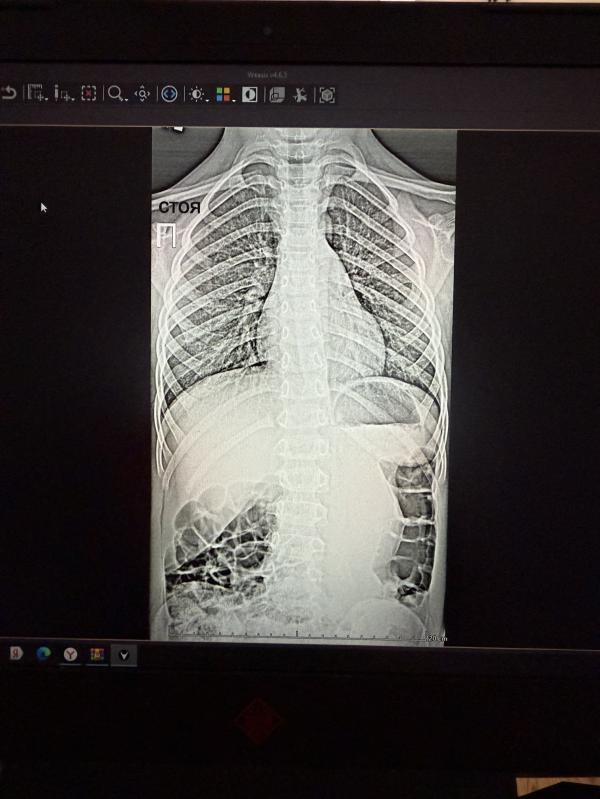

У сына обнаружили сколиоз. По рентгену ставят 2 степень 😭 после рентгена у ортопеда ещё не были, а я себя уже извела. Год назад ортопед не видел проблем со спиной - может, невнимательно осмотрела? В последнее время я как будто замечала разный уровень плеч, но почему-то не сразу придала этому значение.

У кого у детей была схожая ситуация - удалось ли решить проблему? Хотя бы вывести в 1 степень? В последний год он сильно вытянулся (хотя и всегда рост был выше среднего) - может, это могло стать причиной. Я не понимаю, откуда это вообще взялось у дошкольника, который много занимается спортом.